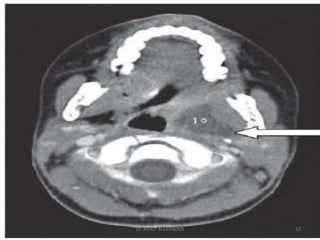

Parapharyngeal abscess

Dr. ASHLY ALEXANDER

51

52

• Treatment

– IV antibiotics

– Correct dehydration

– Analgesics

– Surgery

• External approach

(access along the carotid sheath)

–Transverse submandibular incision

– Mosher’s T-shaped incision

53